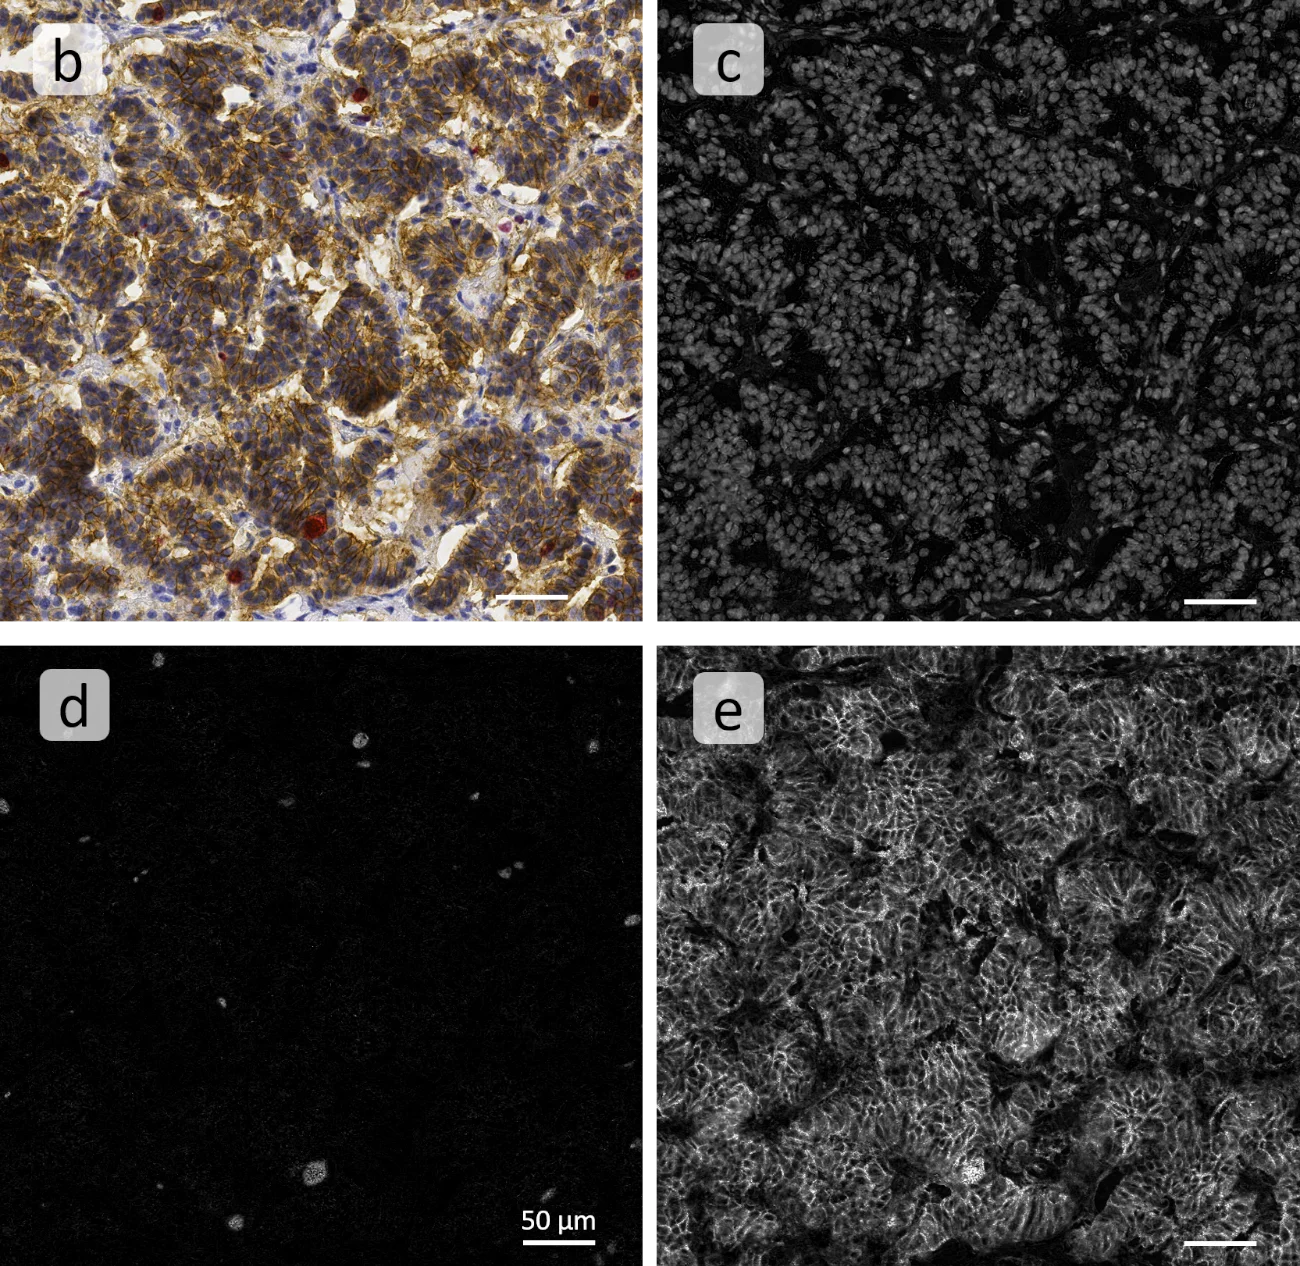

The first step of the analysis was the generation of grey images for the markers, utilized automatically by TG´s color separation algorithm, based on the marker color and intensity: (b) shows the original image, (c) is the nuclei grey image, (d) and (e) represent unmixed gray channels for Ki67 and NCAM correspondingly.

Next, these channels are used as the basis for cell segmentation (nuclei) and marker detection (Ki67, NCAM): (f) is the original image, (g) shows Ki67+ cells in turquoise nuclei mask, and (h) combined overall cell detection in pink, with Ki67+ cells highlighted in turquoise.